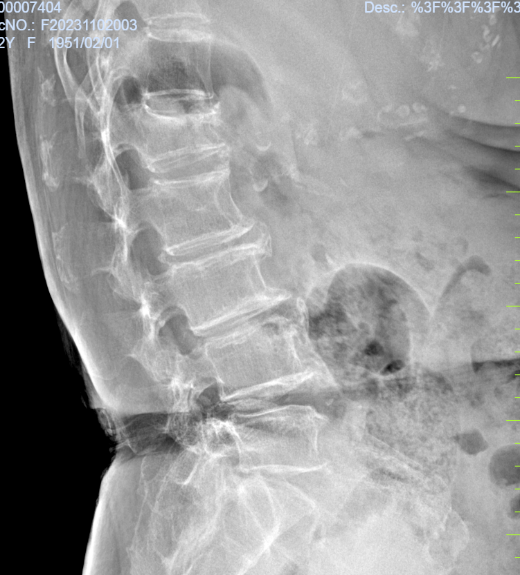

病例三:患者,刘某,女,72岁,因“外伤致腰部及髋部疼痛不适1天”入院。诊断:腰1椎体压缩性骨折,骨质疏松症;行经皮穿刺腰1椎体成形术,手术顺利,术后恢复良好,顺利出院。

腰1椎体压缩性骨 术前X线片 腰1椎体压缩性骨 术前磁共振

腰1椎体压缩性骨 术后X线片